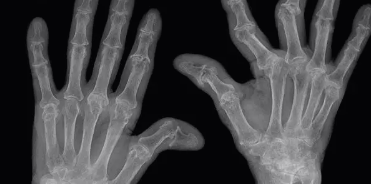

그럼 병원에서는 어떻게 진단할까요? 단순히 X-ray만 찍는 게 아니고, 여러 가지 검사를 종합적으로 진행해요.

- 영상 검사 : X-ray, 초음파, MRI 등을 통해 관절 손상 정도를 살펴봐요

빠른 진단이 중요한 이유는, 류마티스 관절염은 시간이 지나면 관절이 망가져서 되돌릴 수 없게 되기 때문이에요. 초기에 발견해서 치료를 시작하면 손가락 변형을 막을 수 있어요.